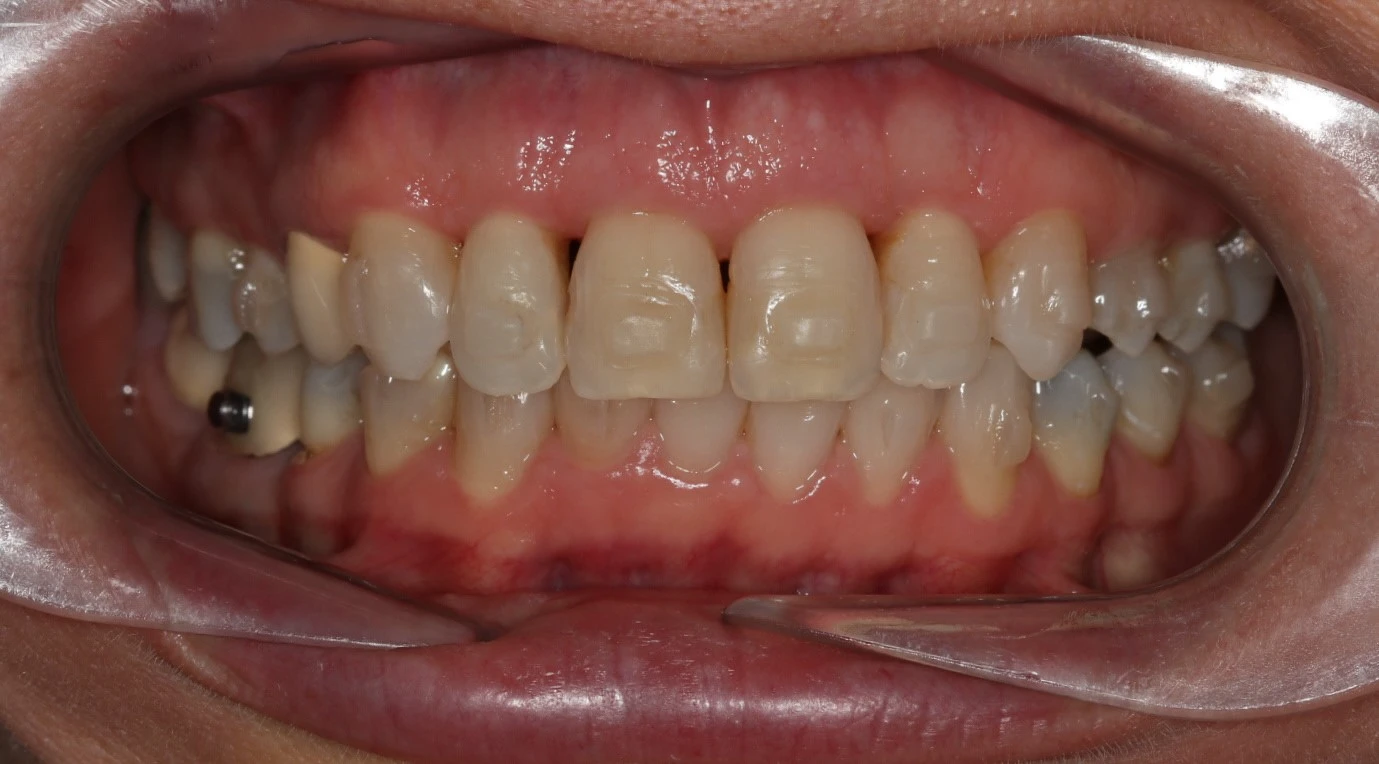

Clear aligner attachments give more precise results. They allow the aligners to grip onto the teeth for more accurate tooth movement in a faster time than without attachments.

Attachments are tooth coloured, much smaller than braces and won’t damage your teeth when they are polished away at the end of treatment.

Sometimes when crowded and or rotated teeth are re-aligned, dark triangles can appear between the teeth. This is due to receded gums or lack of gum tissues around the teeth which becomes noticeable when the teeth are moved.

Unfortunately these dark triangles can spoil the smile aesthetics.

The main treatment to reduce these dark triangles is reshaping the teeth so that they are less triangular in shape.

The other option is to ask your dentist to add composite bonding between the teeth.